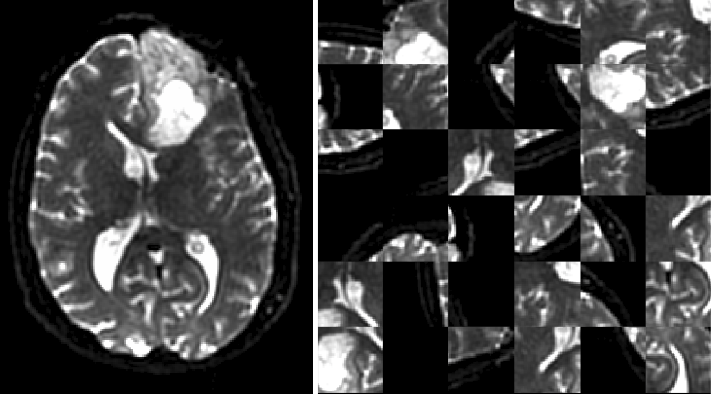

Current Augmentation objects available include 2D and 3D flips and rotations, intensity scaling and shifting, 3D patch extraction, channel-wise dropout, and nearest-neighbor downsampling. Patch extraction can be performed to preferentially select patches that match certain criteria, such as being near a tissue of interest (Figure 4).

Provided that these software challenges are overcome, the unique nature of medical imaging data produces additional barriers to the neuroscience researcher. Medical images often require numerous and highly-specialized pre- and post-processing techniques, each of which can unpredictably affect the performance of deep learning algorithms. Imaging data is often in higher resolution, as with digital pathology, or in higher dimensions, as with magnetic resonance (MR) imaging data, than traditional imaging datasets. As a result, images may need to be divided into patches, slices, or other representations before being input to a deep learning algorithm, and the specific implementation of these methods can have a significant impact on that algorithms’ performance. Post-processing techniques, particularly for segmentation algorithms, can have a significant effect on an algorithm’s practical utility in the clinic. All of these problems are even more highly elaborated in the field neuroimaging, which often has imaging sequence-specific or disease-specific processing steps for medical data. Even when such processing steps are described, a subtle change in their implementation can have significant effects on the accuracy and consistency of a deep learning algorithm.